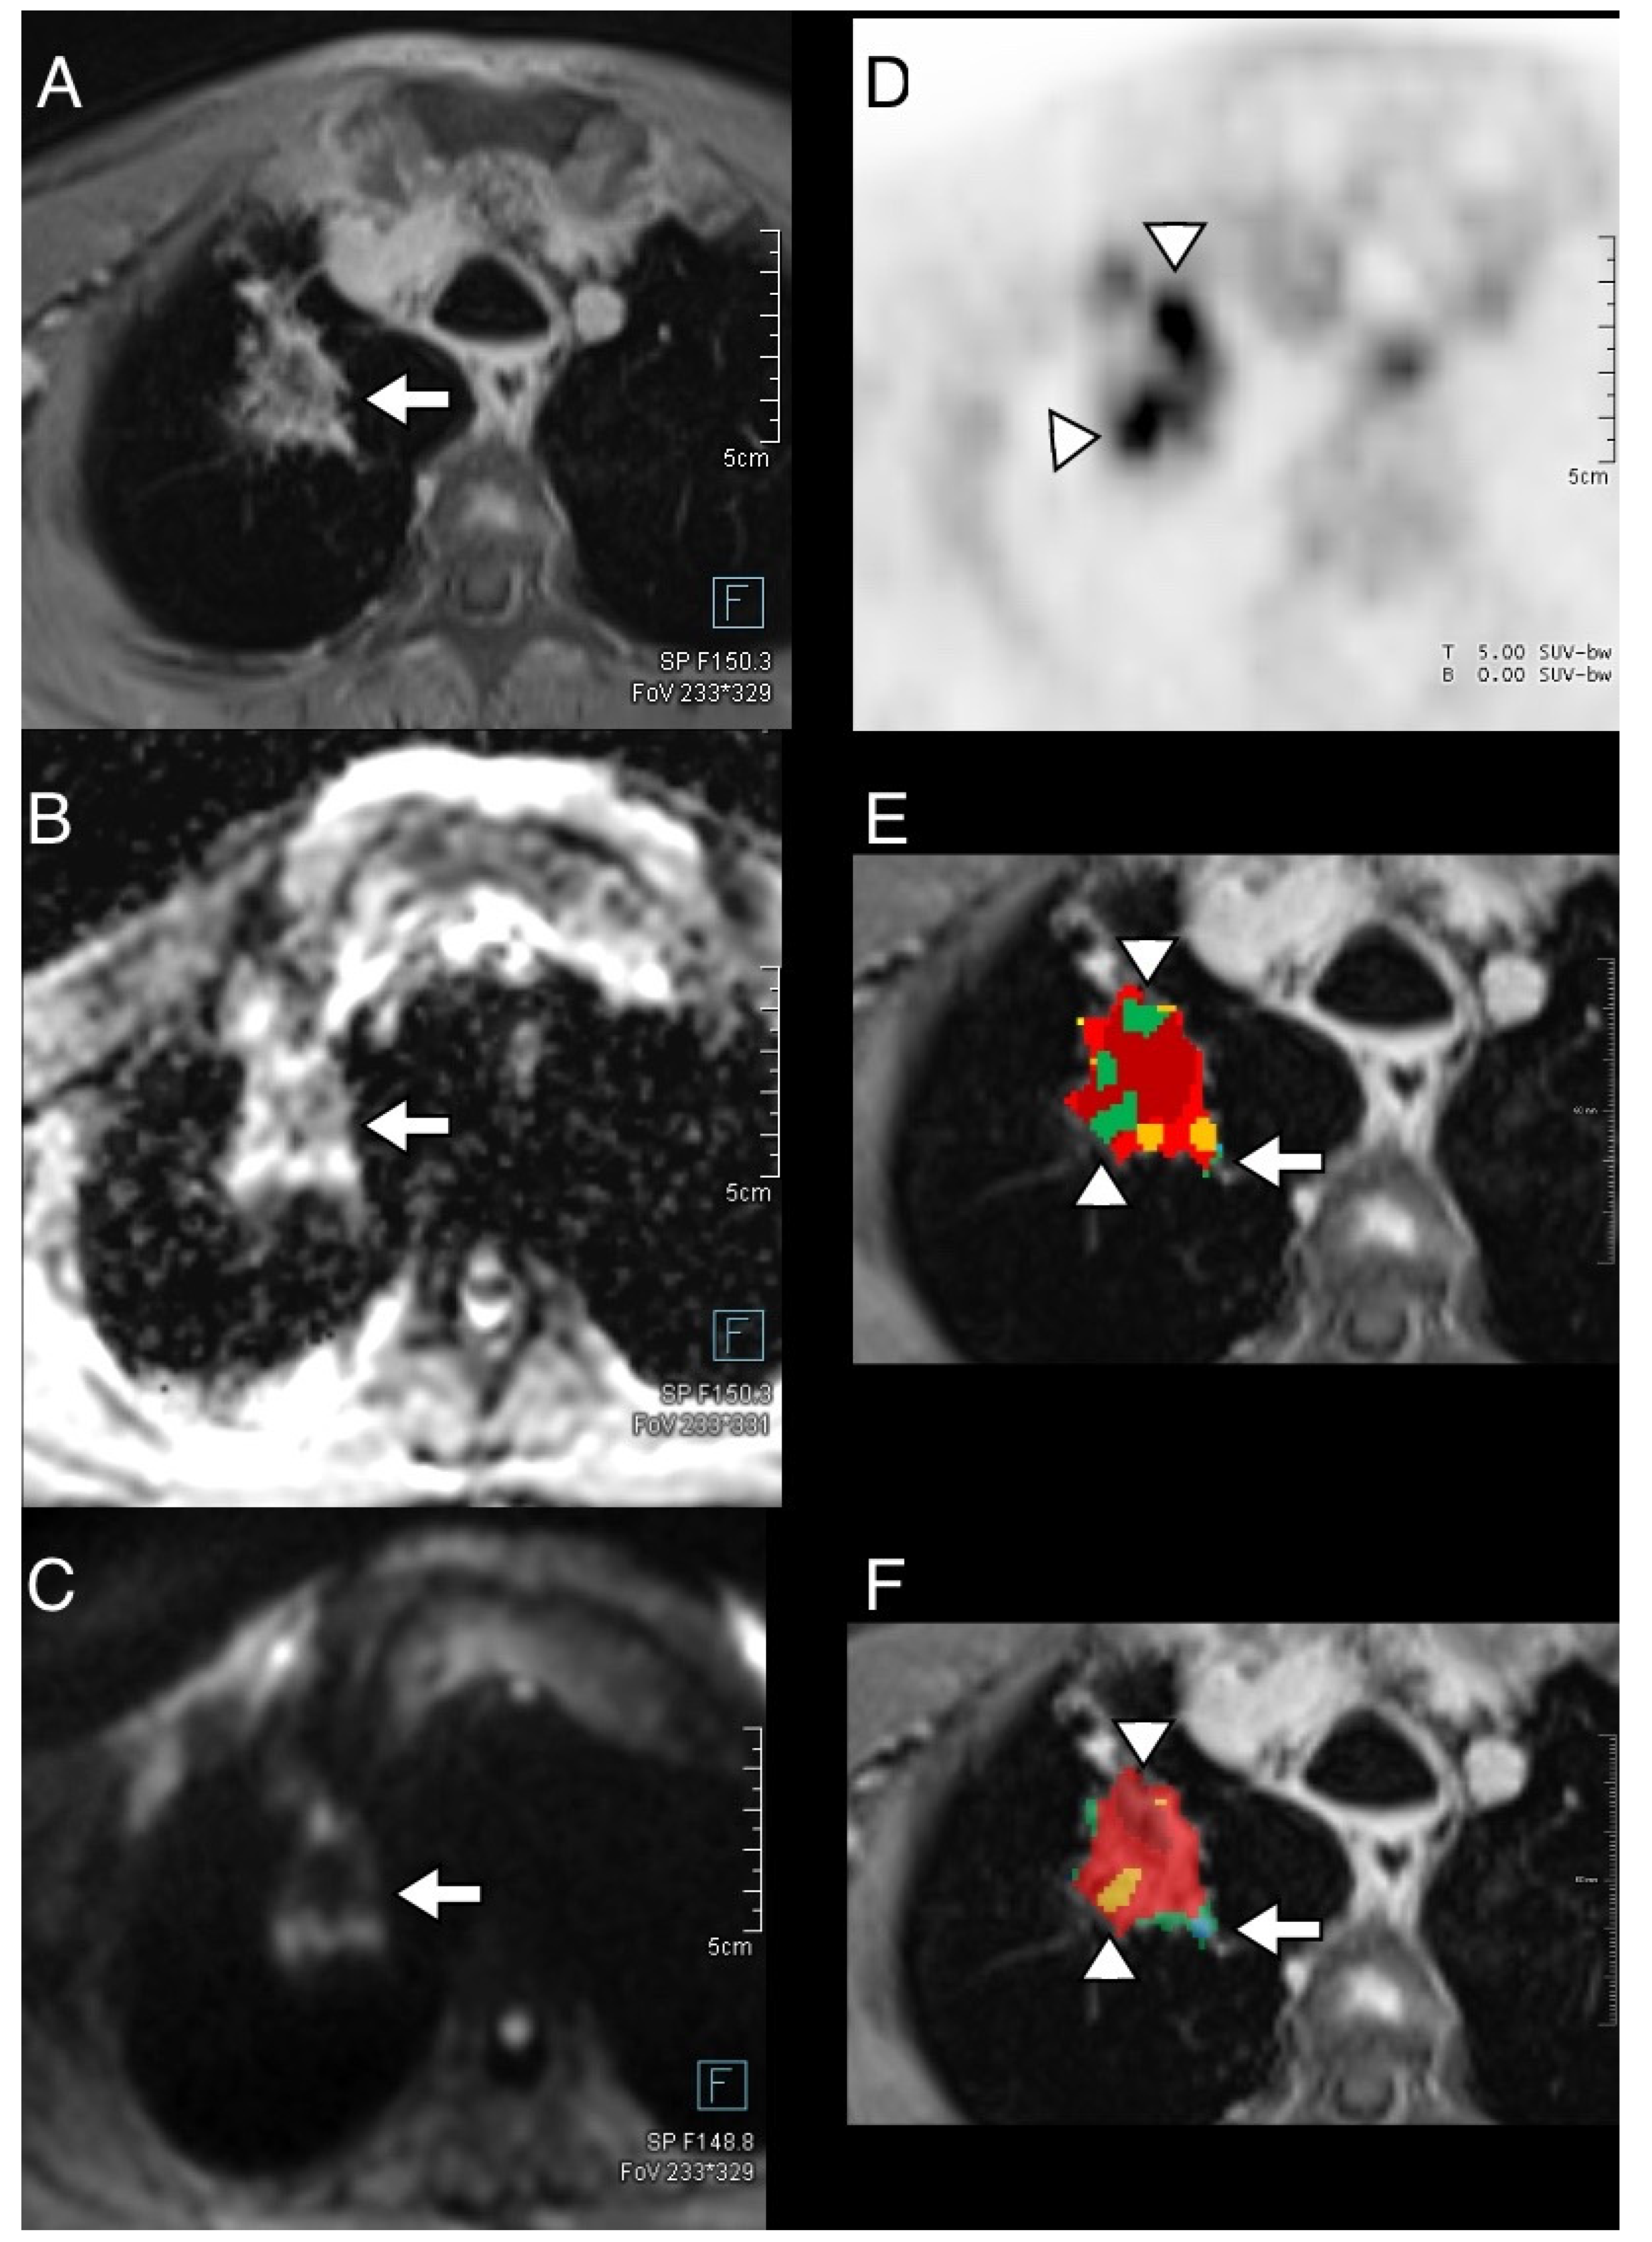

3.4. Thoracic Tumor Segmentation and Registration

3.5. Plausibility of DWI and PET Images